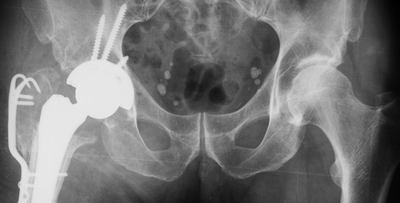

Коллеги прошу прощения, технические неполадки. Вот первый снимок без нагрузки.

КТ конечно было сделано. И вот результаты.

Обзорная рентгенография нижних конечностей.

Мне кажется, я знаю, о ком речь...

Неделю назад эта пациентка была у меня на консультации.

Сделал ей КТ.

С удивлением узнала, что перелом в области шейки у неё не сросся, хотя на рентгенограмме тех лет так оно и есть.

Поверила на слово врачам - сказали, что срослось. Слово - лечит:))

КТ - во вложении.

Поскольку основная жалоба на укорочение конечности, то я ей предложил удлинить голень. Величину удлинения обсудили - в пределах 4 см.

Она решила пойти по "большому кругу" в плане консультаций. Думаю, еще где-нибудь всплывет.

Не стал бы называть случай интереснейшим, но не совсем типичный, это да...

Интересна функциональная адаптация - практически полная функция того, что раньше было тазобедренным суставом.